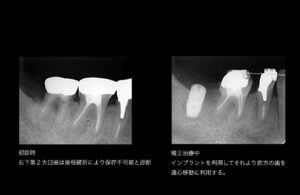

右下第2大臼歯は過度な負担と金属冠のため歯根破折を起こしていた。抜歯を行い矯正期間中に歯槽骨が回復するのを待ってインプラントにて修復を行う。